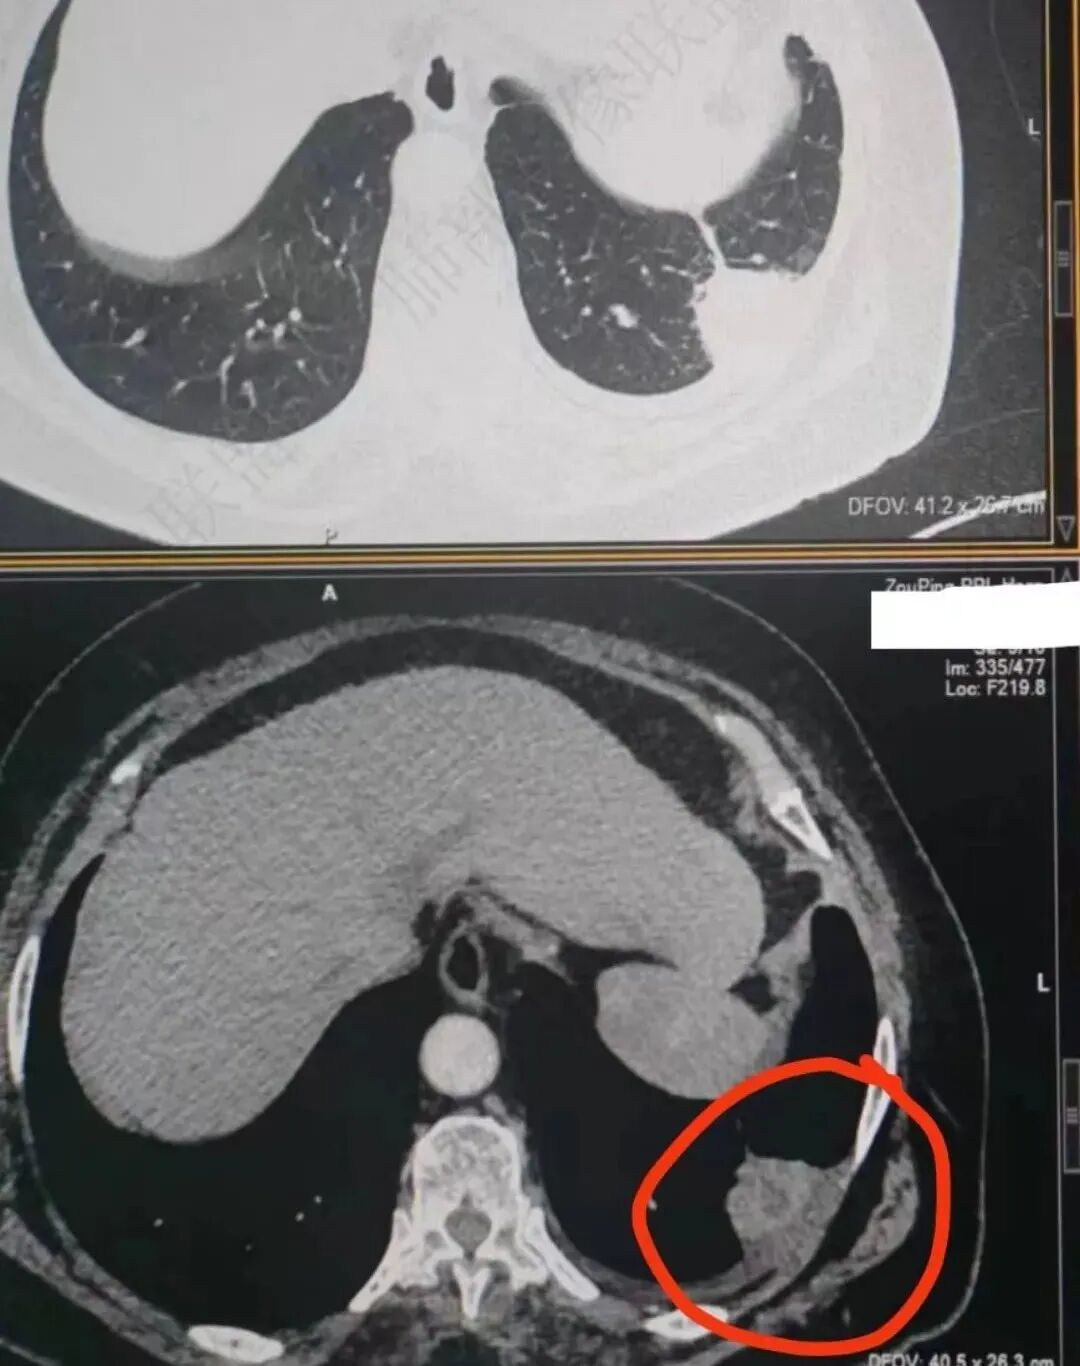

这就栽赃。都突到外面去了。

看看这个,骨头都侵袭了。

我只是邓较瘦:南大这个我感觉局部似乎是栽赃呢 箭头那里是啥?

南边:栽赃是这样过去的,中间不会脂肪间隙清晰。

胸壁的组织,除非你怀疑胸壁转移结节。

转移淋巴结。

局部侵犯。有差异。

我只是邓较瘦:这个是侵犯出去不是淋巴结吧?

南边:不是,你看看强化与淋巴结不一致。

我只是邓较瘦:强化与肿瘤差不多。

南边:是。